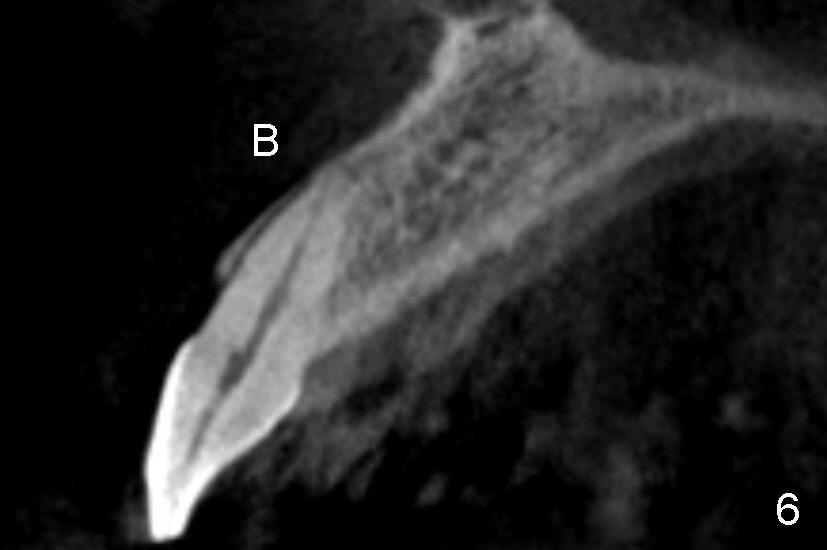

图六是CT扫描,显示中切牙以及牙槽骨矢状切面(B:颊侧)。拔牙后,如果我们沿着牙齿长轴钻洞(图七:红长箭头),势必将使菲薄的颊侧骨板穿破(X),其实牙槽窝舌侧(L)有很多骨质。钻洞必须在舌侧骨板中点开始(箭头),但是舌侧骨板是一个斜坡,起初钻洞必须与舌侧骨板垂直(图八:箭头),否则钻头会打滑。一旦钻头初步进入骨质,必须改变钻头方向:沿着牙槽骨长轴前进(图九:长箭头),否则舌侧骨板也会穿孔(沿原来短箭头)。边钻洞边用拇指和食指握住颊舌侧骨板,把握钻头方向。图十显示上颌中切牙处五乘二十毫米锥形植牙设计。